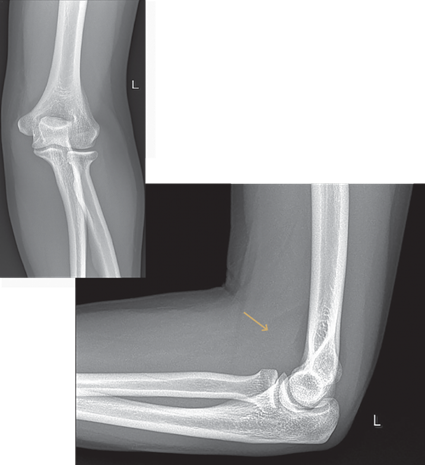

Paciente del sexo femenino, de 18 años de edad, que acudió al servicio de urgencias de su hospital. Refirió haber caído de su propia altura al estar practicando deporte y que al caer alcanzó a estirar el brazo izquierdo para tratar de detener la caía, tras lo cual presentó importante dolor en el codo, mismo que se intensificó al tratar de movilizarlo, con presencia de hematoma en cara anterior del codo.

¿Cómo se conoce al signo radiológico que se observa en la radiografía lateral de codo?

Signo de la vela o almohadilla grasa